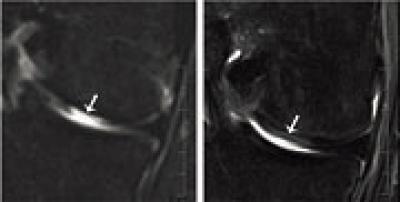

This figure shows an MRI of a defect tissue site before (left) and four months after (right) transplantation. Fig: University of Basel, Department of Biomedicine

Cartilage cells from the nasal septum (nasal chondrocytes) have a distinct capacity to generate a new cartilage tissue after their expansion in culture. In an ongoing clinical study, the researchers have so far taken small biopsies (6 millimeters in diameter) from the nasal septum from seven out of 25 patients below the age of 55 years and then isolated the cartilage cells. They cultured and multiplied the cells and then applied them to a scaffold in order to engineer a cartilage graft the size of 30 x 40 millimeters.

A few weeks later they removed the damaged cartilage tissue of the patients' knees and replaced it with the engineered and tailored tissue from the nose. In a previous clinical study conducted in cooperation with plastic surgeons and using the same method, the researchers from Basel recently already successfully reconstructed nasal wings affected by tumors.

While the primary target of the ongoing clinical study at the University Hospital of Basel is to confirm the safety and feasibility of cartilage grafts engineered from nasal cells when transplanted into joint, the clinical effectiveness assessed until now is highly promising.